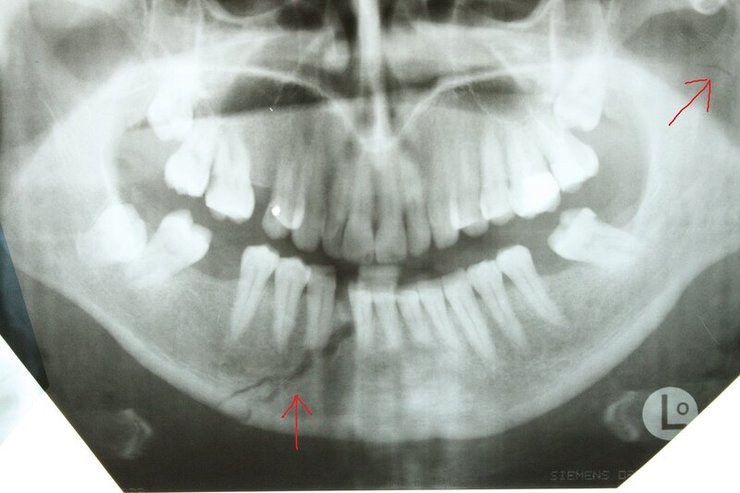

Сын главы Чечни Рамзана Кадырова Адам Кадыров мог сломать челюсть, когда попал в ДТП. Кроме этого, он имеет еще ряд менее значительных травм.

Авторы отмечают, что характерный для такой травмы отек лица спадает лишь через 1-2 недели. А на то, чтобы снять фиксацию челюсти, понадобится примерно месяц.

Челюсть Адама Кадырова NIYSO

Челюсть Адама Кадырова NIYSO

Также в результате аварии у Кадырова-младшего могли появиться рваные раны, рассечения, разрывы кожи и гематомы. Из-за этого может понадобиться еще несколько недель, чтобы скрыть последствия аварии.